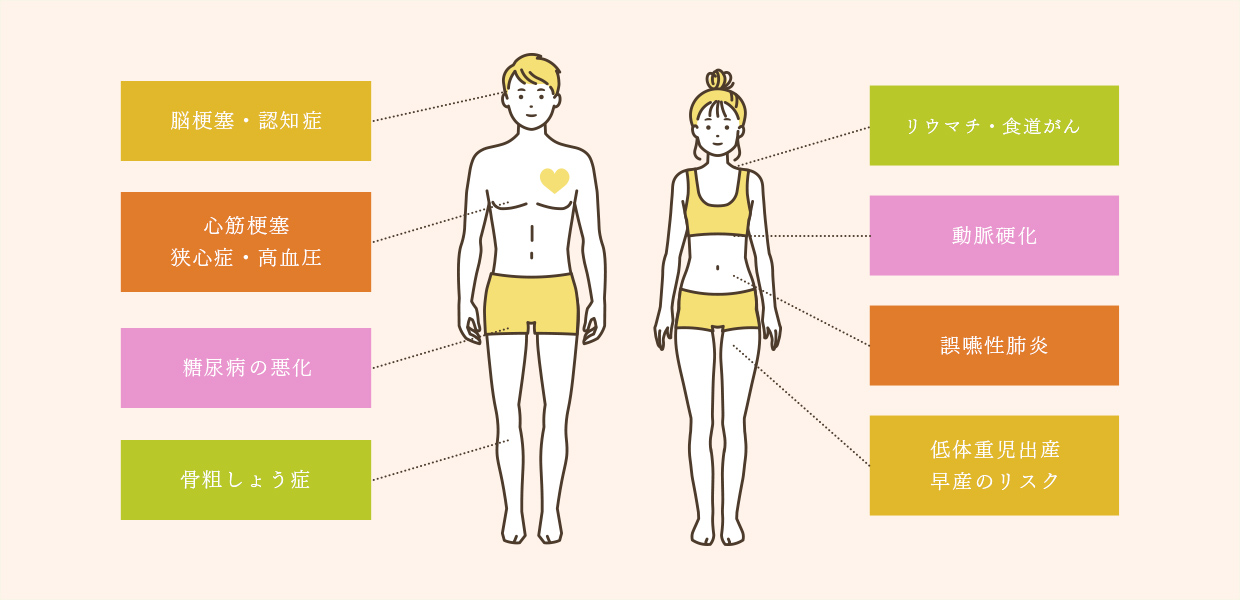

歯周病と全身疾患の関係

- 歯周病は全身疾患の

リスクを高めてしまいます 歯周病自体は口腔内の疾患ですが、歯周病が引き金となって生じる全身疾患があることはご存知でしょうか。脳卒中や骨粗鬆症、糖尿病などの全身疾患は、歯周病の悪化により全身に歯周病菌が巡ることで発症するリスクがあります。

糖尿病との関係

糖尿病をお持ちのかたは、歯周病を発症するリスクが高くなると言われています。また逆に、歯周病を患っているかたは糖尿病を悪化させやすいこともわかっています。

脳梗塞・心筋梗塞との関係

歯周ポケットの炎症部を介して歯周病菌が血管に入り込むと、動脈硬化を進行させてしまい、脳梗塞や心筋梗塞のリスクが高まります。また、細菌性の心内膜炎の原因になることも報告されています。

誤嚥性肺炎との関係

飲食物の一部が誤って肺に入った際、歯周病菌が一緒に入り込むと肺炎を起こす原因になります。特に、飲み込む力が低下しているかたは注意が必要です。